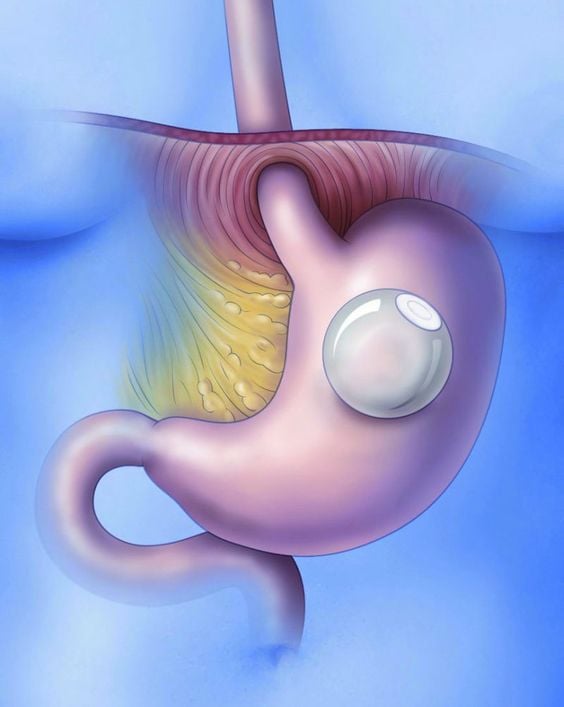

تعد مشكلة زيادة الوزن من التحديات التي يعاني منها الكثيرون، وقد يكون من الصعب إيجاد الحلول الفعّالة التي توفر نتائج طويلة الأمد. في الآونة الأخيرة، أصبح بالون المعدة في الرياض واحدًا من أبرز الحلول المتاحة، لما له من فوائد في مساعدة الأفراد على فقدان...

تعتبر عملية بالون المعدة في الرياض من الخيارات الشائعة للأشخاص الذين يسعون لفقدان الوزن بطريقة غير جراحية. تتيح هذه التقنية للعديد من الأشخاص تحقيق أهدافهم في إنقاص الوزن وتحسين نمط حياتهم الصحي دون الحاجة إلى جراحة معقدة. في هذا المقال، نستعرض تجارب...